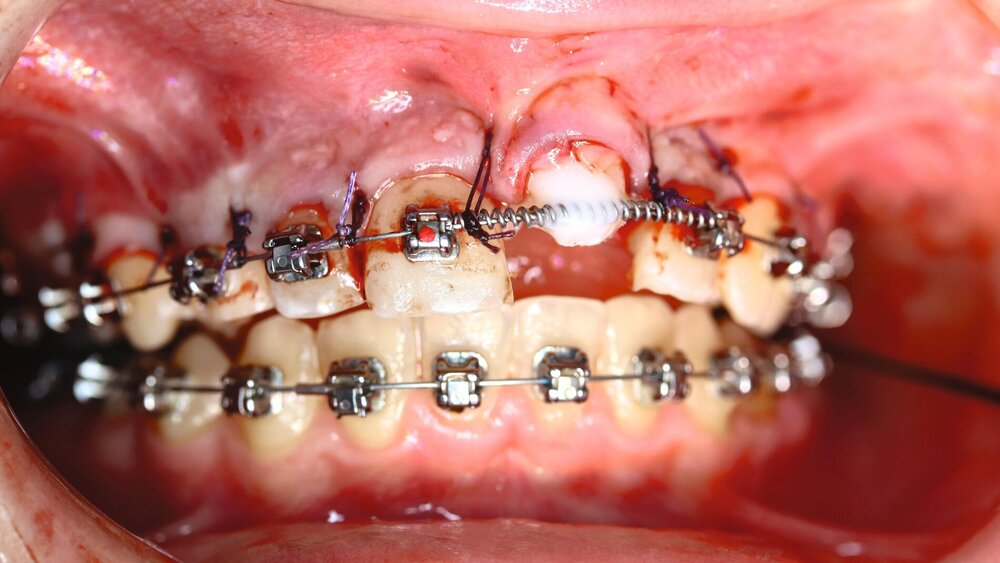

Wir entschieden uns für ein zweizeitiges Vorgehen mit Entfernung des Zahnes 21 und Ausräumung der ausgedehnten entzündlichen Läsion im apikalen Bereich mit Anfrischung des Knochens, um so eine entzündungsfreie Situation vor Transplantation zu erreichen. Der Zahn 21 wurde provisorisch als Pontic wieder eingesetzt, um eine weitere Retraktion des Weichgewebes in regio 21 zu vermeiden (Abbildung 3B).

Auf Empfehlung des mitbehandelnden Kieferorthopäden sollte der natürliche Lückenschluss in regio 53 belassen und die autogene Transplantation des verlagerten Eckzahns 13 an die Stelle des verloren gegangenen Zahnes 21 durchgeführt werden. Der Eckzahn 13 wurde etwa einen Monat später in die Region 21 transplantiert und am zuvor eingebrachten kieferorthopädischen Bogen kunststoffadhäsiv fixiert (Abbildung 4).